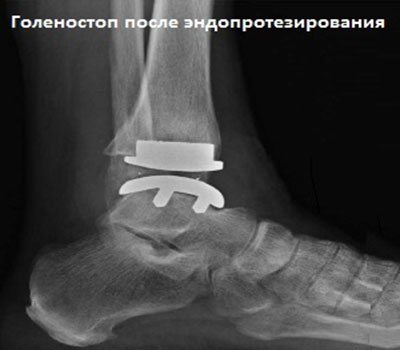

Если артрозо-артритом поражен голеностоп, то пациенту показан артродез, заключающийся в полном обездвиживании сочленения. В последнее время в терапии используются стволовые клетки. Они замещают собой разрушенные участки хрящей, активизируют их регенерацию.

- Артродез – удаление голеностопного сустава. При этом кости стопы и голени как бы сращиваются между собой. После операции подвижность соединения будет сильно ограничена.

- Эндопротезирование – замена сустава протезом. Подвижность голеностопа после операции восстанавливается полностью.